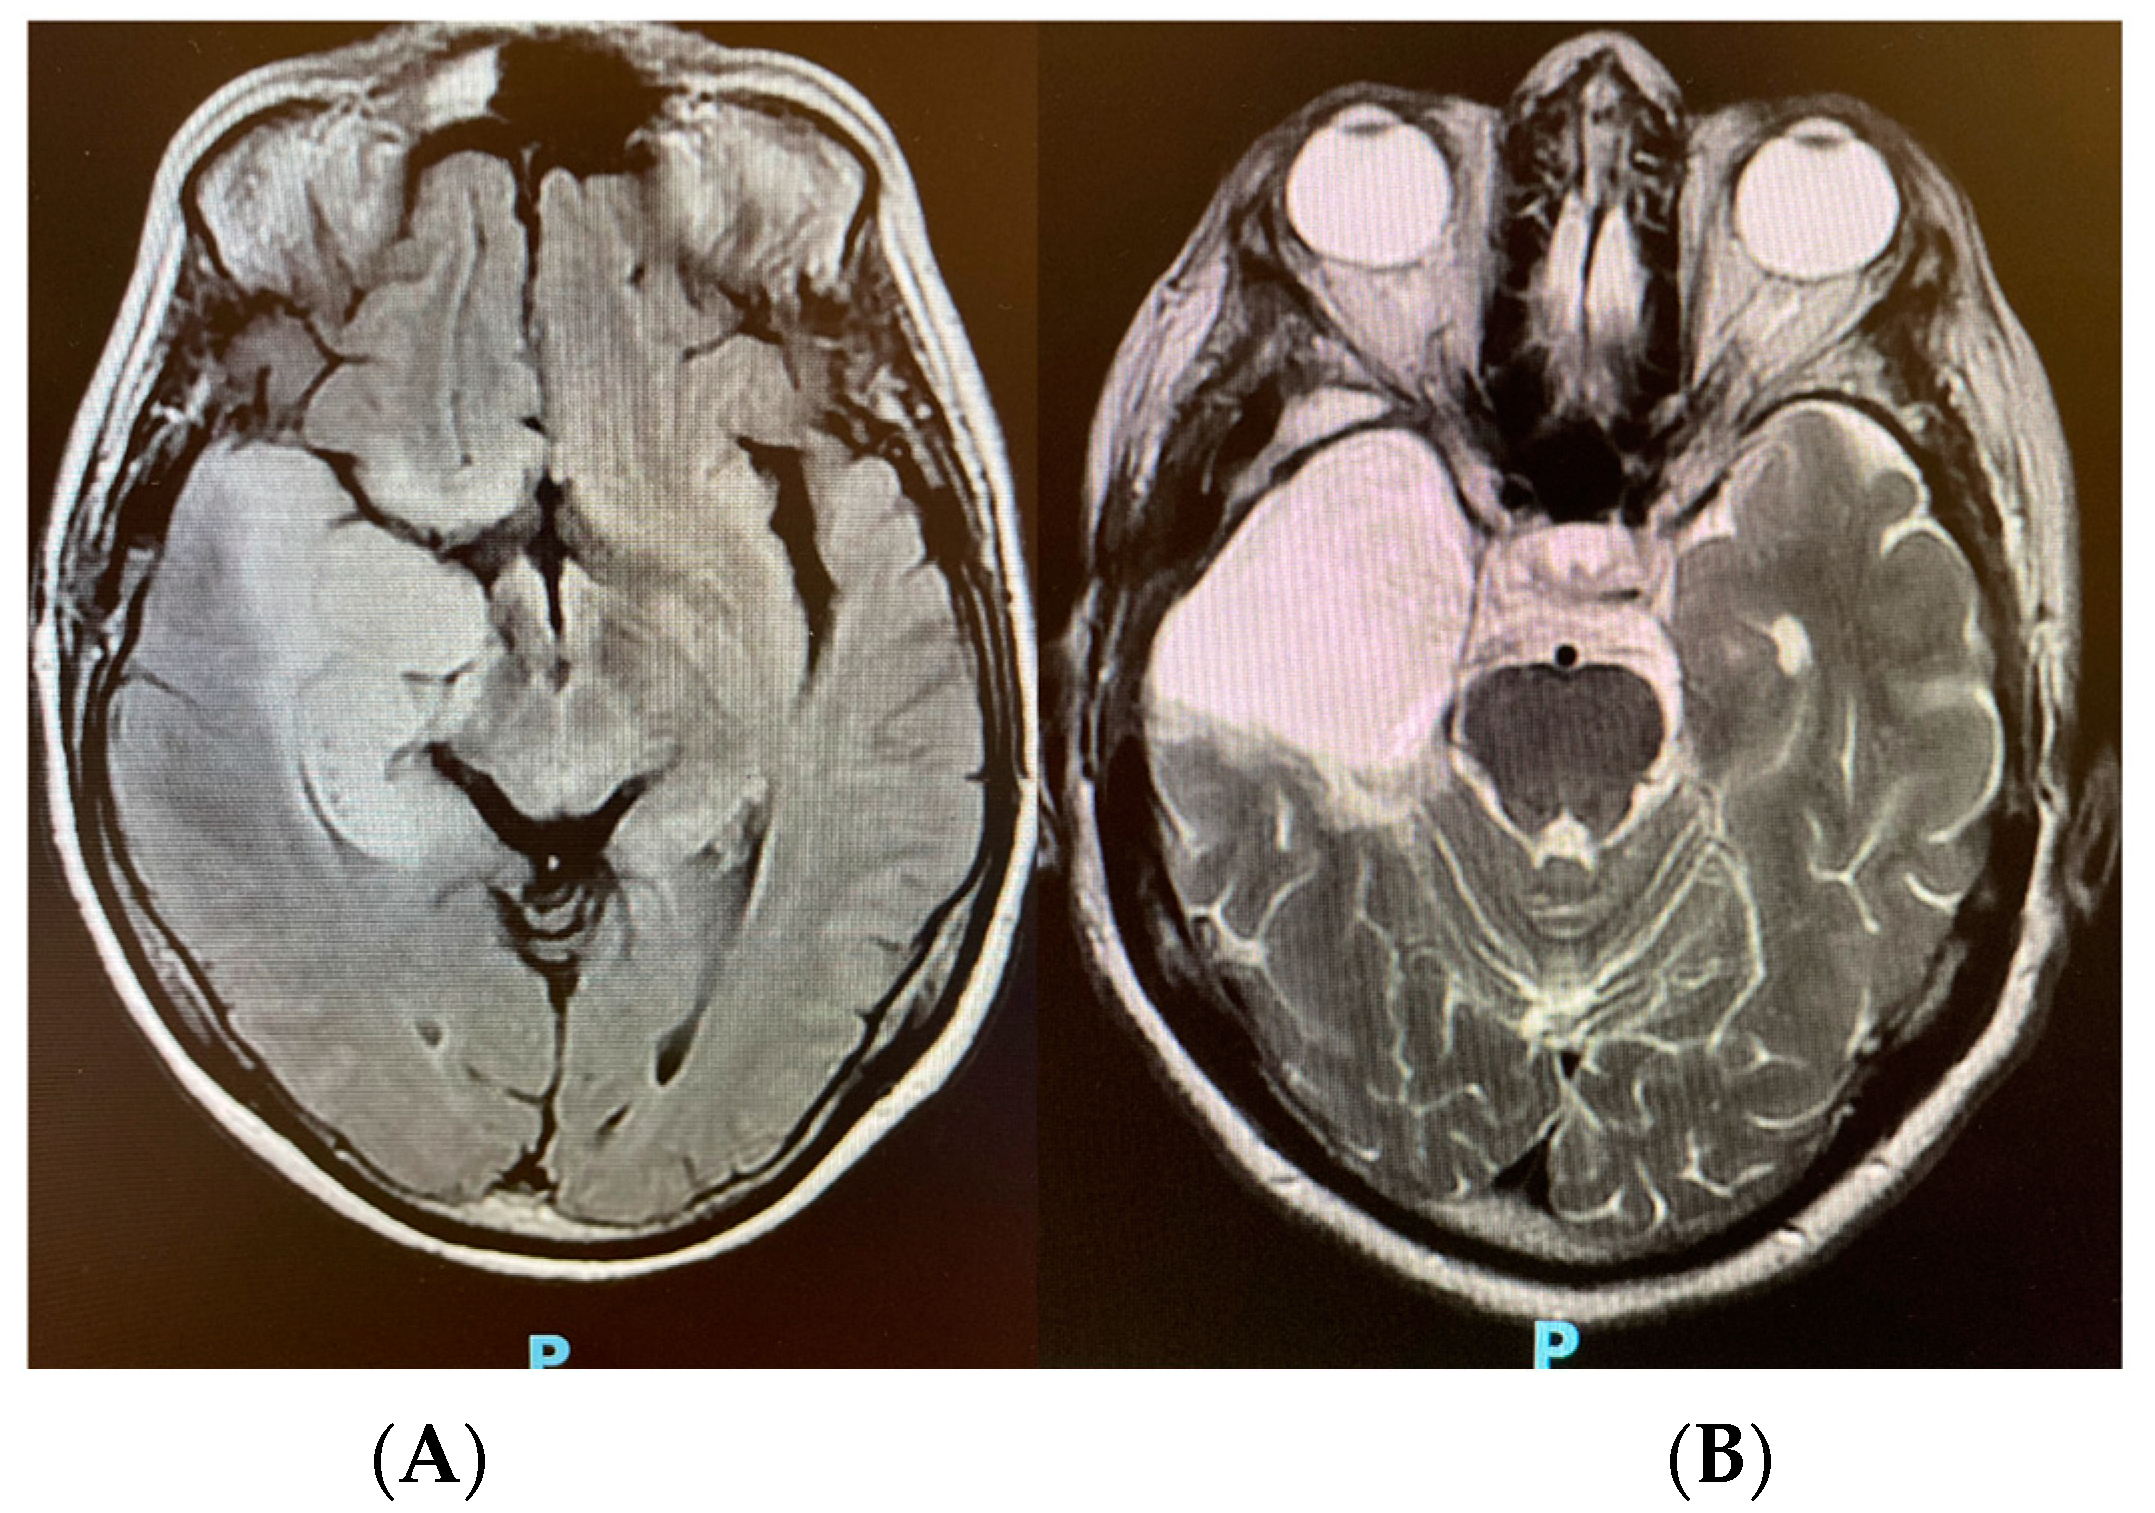

2. Case Presentation